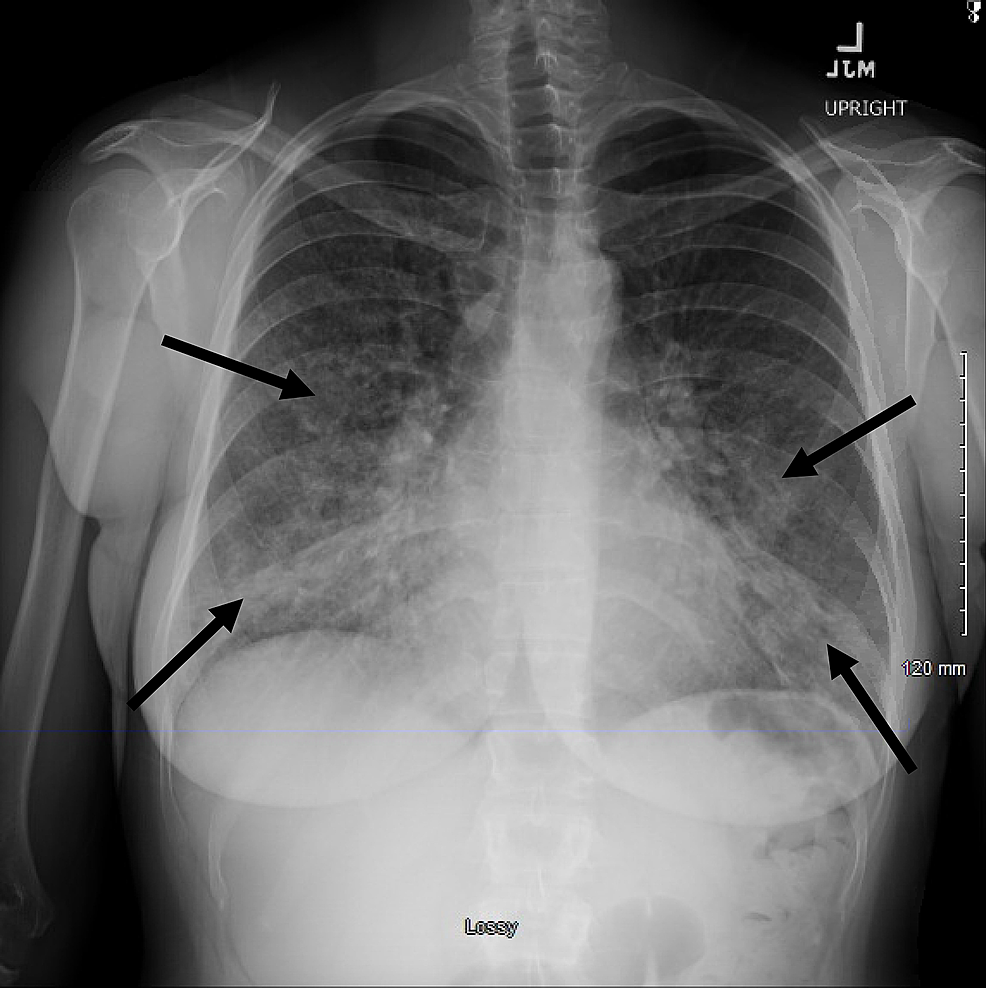

Posteroanterior chest Xray of acute idiopathic eosinophilic pneumonia Chest X Ray Eosinophilic Pneumonia Characteristic imaging findings are often detected with chest radiography, and ct best shows parenchymal abnormalities. Eosinophilic lung diseases are a heterogeneous group of disorders that are characterized by excess infiltration of. The integration of clinical, radiologic, and. Diagnosis of eosinophilic pulmonary diseases. Eosinophilic pneumonia represents a heterogeneous group of lung disorders characterized by the presence of peripheral blood eosinophilia (defined. Chest X Ray Eosinophilic Pneumonia.